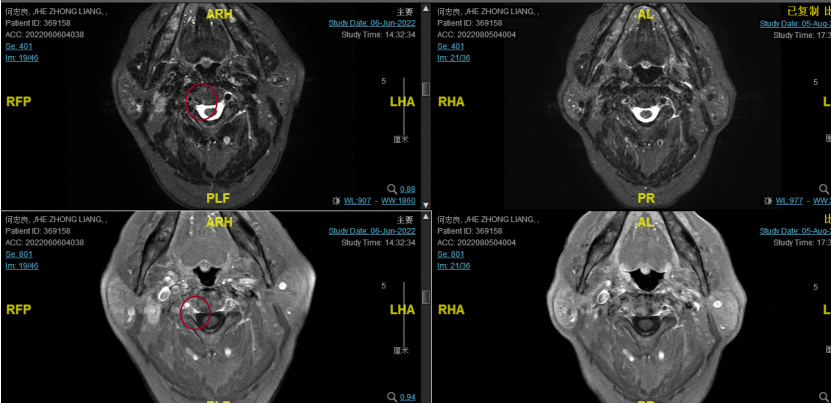

后患者至江苏省肿瘤医院放疗科就诊,2022-06-06完善头颅MR检查:

修正诊断:鼻咽癌T3N1M0,Ⅲ期。

2022-06-29行鼻咽IGRT放疗:GTV1 68Gy/32f、GTV2 68Gy/32f、CTV1 60Gy/32f、CTV2 50.4Gy/28f。期间同步斯鲁利单抗+尼妥珠单抗+恩度治疗。

2022-08-05(放疗近结束)复查MR,疗效评价:CR。鼻咽部肿物及咽后转移淋巴结颈部转移淋巴结均达到CR。